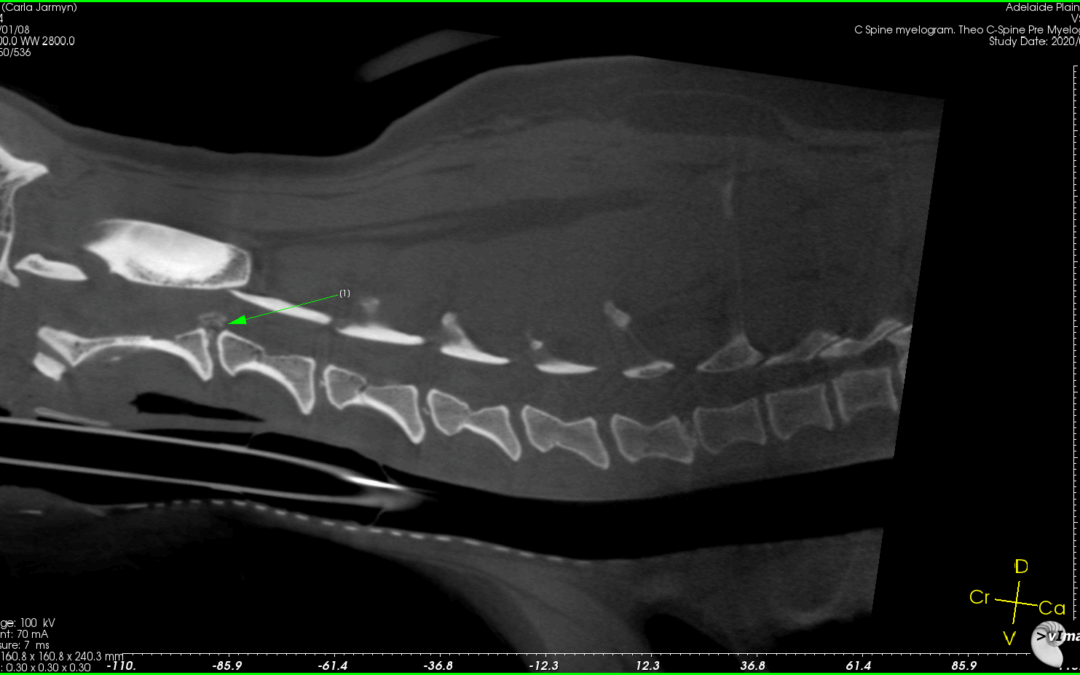

CT Image of disc protusion at C2-C3